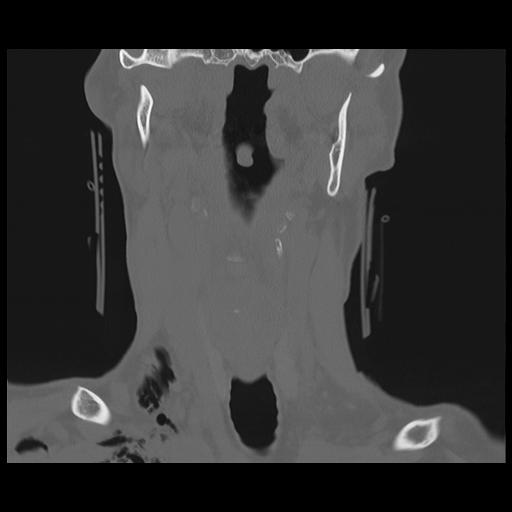

16 HUESO,,Coronal,2.000,HUESO,Coronal,